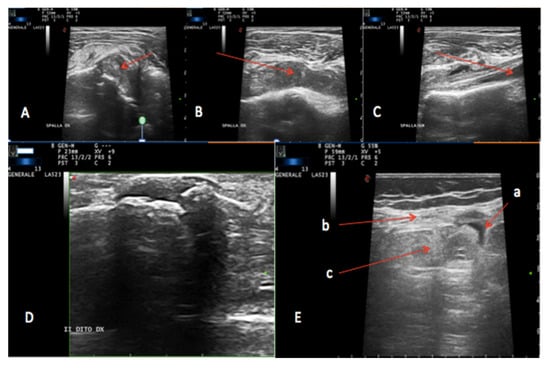

:1. Introduction